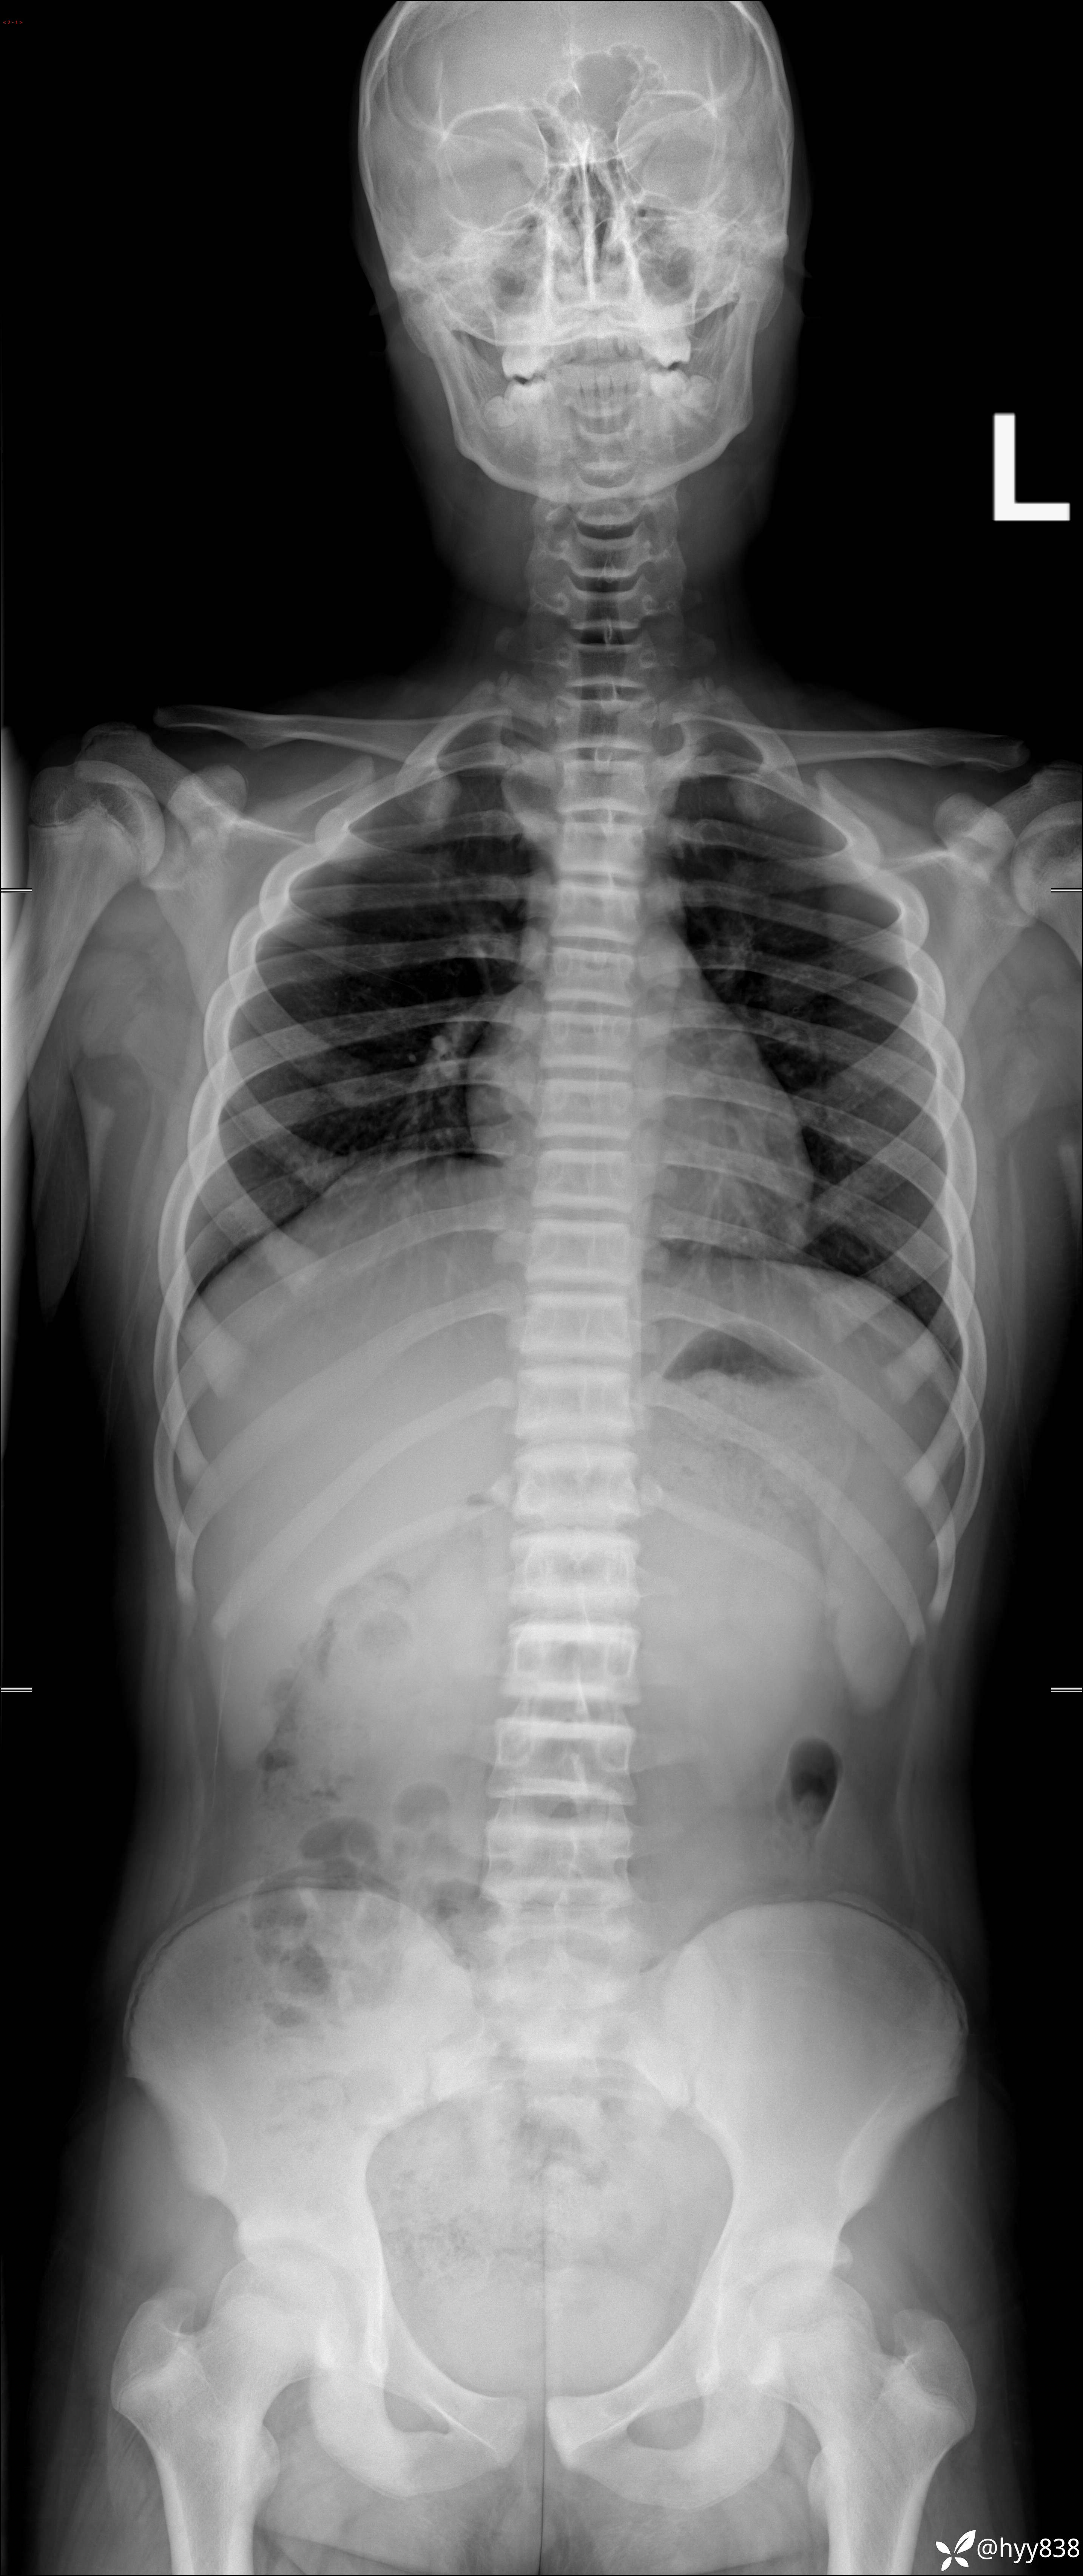

性别:男

年龄:13岁

简要病史:脊柱侧弯复诊

颈椎、胸椎、腰椎正侧位片